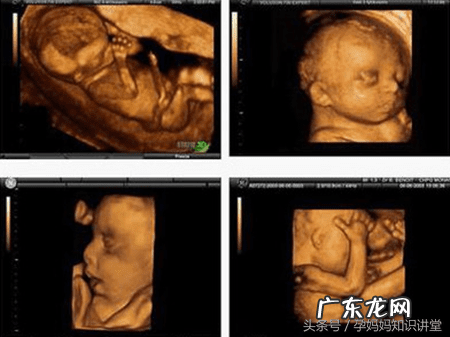

四维彩超提供了包括腹部、血管、小器官、产科、妇科、胎儿彩超图泌尿科、新生儿和儿科等多领域的多方面的应用 。其结果是:能够显示您未出生的宝宝的实时动态活动图像,或者其它人体内脏器官的实时活动图像 。

文章插图